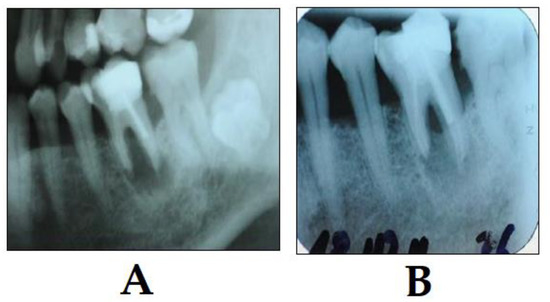

3.5. PDT in Implantology

- Khammissa, R.A.G.; Feller, L.; Meyerov, R.; Lemmer, J. Peri-implant mucositis and peri-implantitis: Bacterial infection. SADJ 2012, 67, 70, 72–74. [Google Scholar]

- Prathapachandran, J.; Suresh, N. Management of peri-implantitis. Dent. Res. J. (Isfahan) 2012, 9, 516–521. [Google Scholar] [CrossRef]

- Dörtbudak, O.; Haas, R.; Bernhart, T.; Mailath-Pokorny, G. Lethal photosensitization for decontamination of implant surfaces in the treatment of peri-implantitis. Clin. Oral Implants Res. 2001, 12, 104–108. [Google Scholar] [CrossRef]

- Sivaramakrishnan, G.; Sridharan, K. Photodynamic therapy for the treatment of peri-implant diseases: A network meta-analysis of randomized controlled trials. Photodiagnosis Photodyn. Ther. 2018, 21, 1–9. [Google Scholar] [CrossRef]